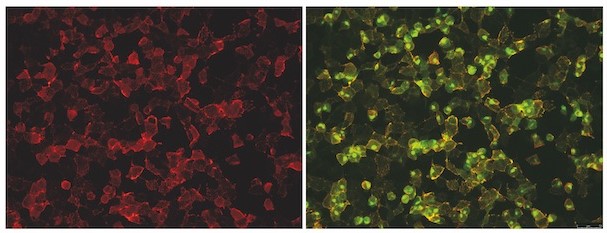

Research Group Translational Neurodegeneration Research

Leader: Univ.-Prof.in Dr.in Nadia Stefanova PhD DSc

The Translational Neurodegeneration research group aims to advance understanding of the molecular mechanisms leading to neurodegeneration in MSA and Parkinson’s disease and to provide preclinical screening and target validation for disease modification in α-synucleinopathies. The group is funded by the Austrian Science Fund (FWF), EU, MSA Coalition and industry grants.

Research Group Translational Neurodegeneration Research

- Lemos M, Venezia S, Refolo V, Heras-Garvin A, Schmidhuber S, Giese A, Leonov A, Ryazanov S, Griesinger C, Galabova G, Staffler G, Wenning GK, Stefanova N: Targeting α-synuclein by PD03 AFFITOPE® and Anle138b rescues neurodegenerative pathology in a model of multiple system atrophy: clinical relevance. TRANSLATIONAL NEURODEGERNATION: 2020; 9(1):38. doi: 10.1186/s40035-020-00217-y.

- Herrera-Vaquero M, Heras-Garvin A, Krismer F, Deleanu R, Boesch S, Wenning GK, Stefanova N: Signs of early cellular dysfunction in multiple system atrophy. NEUROPATHOLOGY AND APPLIED NEUROBIOLOGY: 2020; Sep 6. doi: 10.1111/nan.12661.

- Heras-Garvin A, Weckbecker D, Ryazanov S, Leonov A, Griesinger C, Giese A, Wenning GK, Stefanova N: Anle138b modulates α-synuclein oligomerization and prevents motor decline and neurodegeneration in a mouse model of multiple system atrophy. MOVEMENT DISORDERS: 2019; 34(2):255-263.